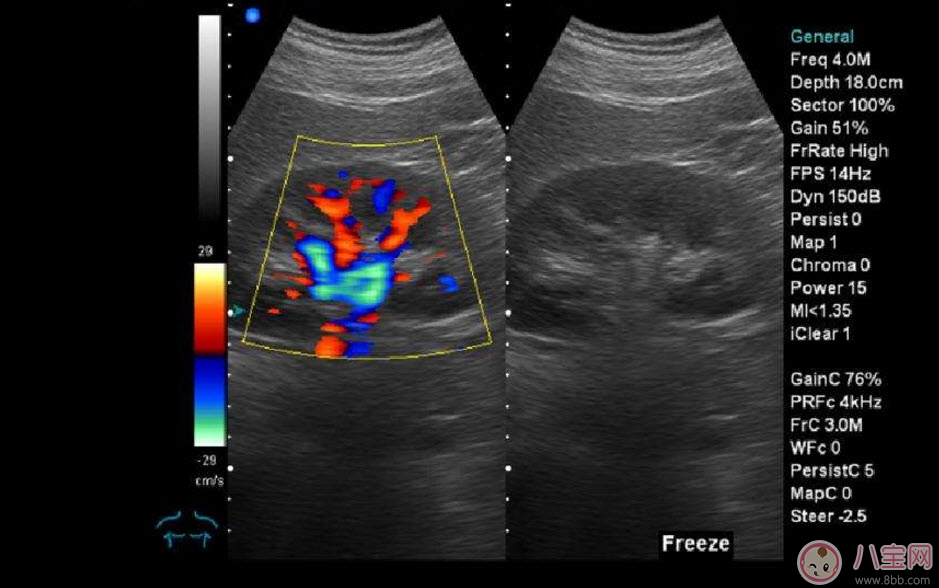

??B超也稱為二維超聲,分為黑白的和彩色的兩種。 彩超其實(shí)還是黑白的,彩超簡(jiǎn)單的說(shuō)就是高清晰度的黑白B超再加上彩色多普勒,既具有二維超聲結(jié)構(gòu)圖像的優(yōu)點(diǎn),又提供了血流動(dòng)力學(xué)的豐富信息。彩超的分辨率會(huì)比一般黑白B超高一些,所以在需要做比較細(xì)致的檢查的時(shí)候,更多的醫(yī)生愿意通過(guò)彩超來(lái)檢查。例如,因?yàn)椴食苡貌噬珮?biāo)注血流,所以當(dāng)臍帶繞頸的時(shí)候就會(huì)看見(jiàn)寶寶的脖子上呈U形或者W形的血流,對(duì)是否臍帶繞頸也就一目了然了。目前用于產(chǎn)檢的超聲波一般都是二維的。

除了能觀察到通過(guò)B超觀察到的一切外,彩超能夠直觀成像,顯示更清晰,結(jié)果也更快速,可發(fā)現(xiàn)異常血流,為診斷胎兒先天性心臟缺陷提供了診斷依據(jù)。價(jià)格要比B超貴,大概在150元左右(會(huì)根據(jù)各地具體情況的不同而上下浮動(dòng))。二維彩超適用于整個(gè)孕期,特別是臨產(chǎn)前。二維彩超的圖像也并非就是彩色的,而是用彩色標(biāo)注心臟、血流等指標(biāo),其實(shí)就是高清晰度的黑白B超再加上彩色多普勒。觀測(cè)到的圖像以紅藍(lán)兩色血流方向?yàn)橹?,面向探頭的呈現(xiàn)紅色,反之為藍(lán)色。這種技術(shù)能夠觀測(cè)到胎兒的血液流動(dòng)情況,有利于及時(shí)發(fā)現(xiàn)胎兒的異常。比如,發(fā)現(xiàn)胎兒頸部有血流環(huán),則意味著發(fā)生了可導(dǎo)致窒息死亡的臍帶繞頸。